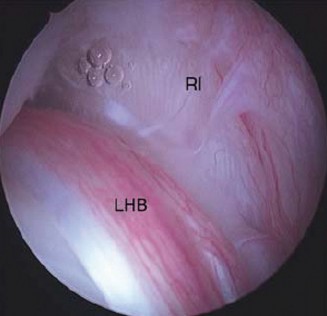

During diagnostic arthroscopy, a thick band of tissue is seen just before the insertion of the supraspinatus and infraspinatus that is running perpendicular to the direction of the muscle fibers. What is this structure called?

Discussion

The correct answer is (C). This structure is a thickening of the coracohumeral ligament that starts anteriorly just posterior to the short head of the biceps tendon on the coracoid process, extends posteriorly through the edge of the avascular zone of the supraspinatus and infraspinatus, and ends at the inferior edge of the infraspinatus. One proposed function of the cable is to act like a cable in a suspension bridge, helping to evenly distribute forces on the humeral head produced by the rotator cuff (see Fig. 2–6).

Figure 2–6_Illustration showing the rotator cable and rotator crescent. B, rotator crescent; C, rotator cable; BT, biceps tendon; I, infraspinatus; S, supraspinatus; TM, teres minor. (Redrawn from Burkhart SS, Lo IKY. Arthroscopic rotator cuff repair. _J Am Acad Orthop Surg. 2006;14(6):333–346.)

The rotator crescent (Answer A) is the thin tissue that exists lateral to the rotator cable medial to the attachment of the supraspinatus and infraspinatus. It is composed on the tendons of these two rotator cuff muscles (see Fig. 2–6).

The rotator interval (Answer B) is the area on the anterior shoulder bordered by the subscapularis inferiorly and the supraspinatus superiorly.